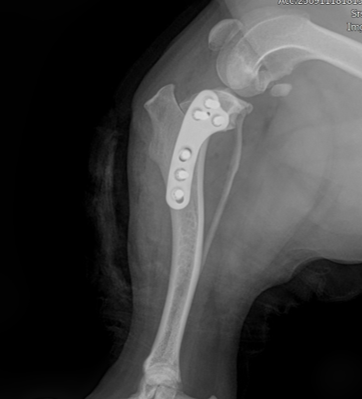

회전한 뼈가 움직이지 않도록 TPLO plate와 screws로 단단하게 고정해 뼈가 안정적으로 붙을 수 있게 합니다.

.png)

수술후 방사선 영상

수술 후 방사선 평가에서는 수술 전 TPA 30°였던 것이 수술 후 4.7°로 교정되어 목표 범위에 가깝고, tibia의 전반적인 정렬도 계획대로 양호하게 확인되었고 절골면이 서로 잘 맞닿아 있었고, 과도한 틈이나 어긋남 없이 양호한 접촉 상태였습니다.